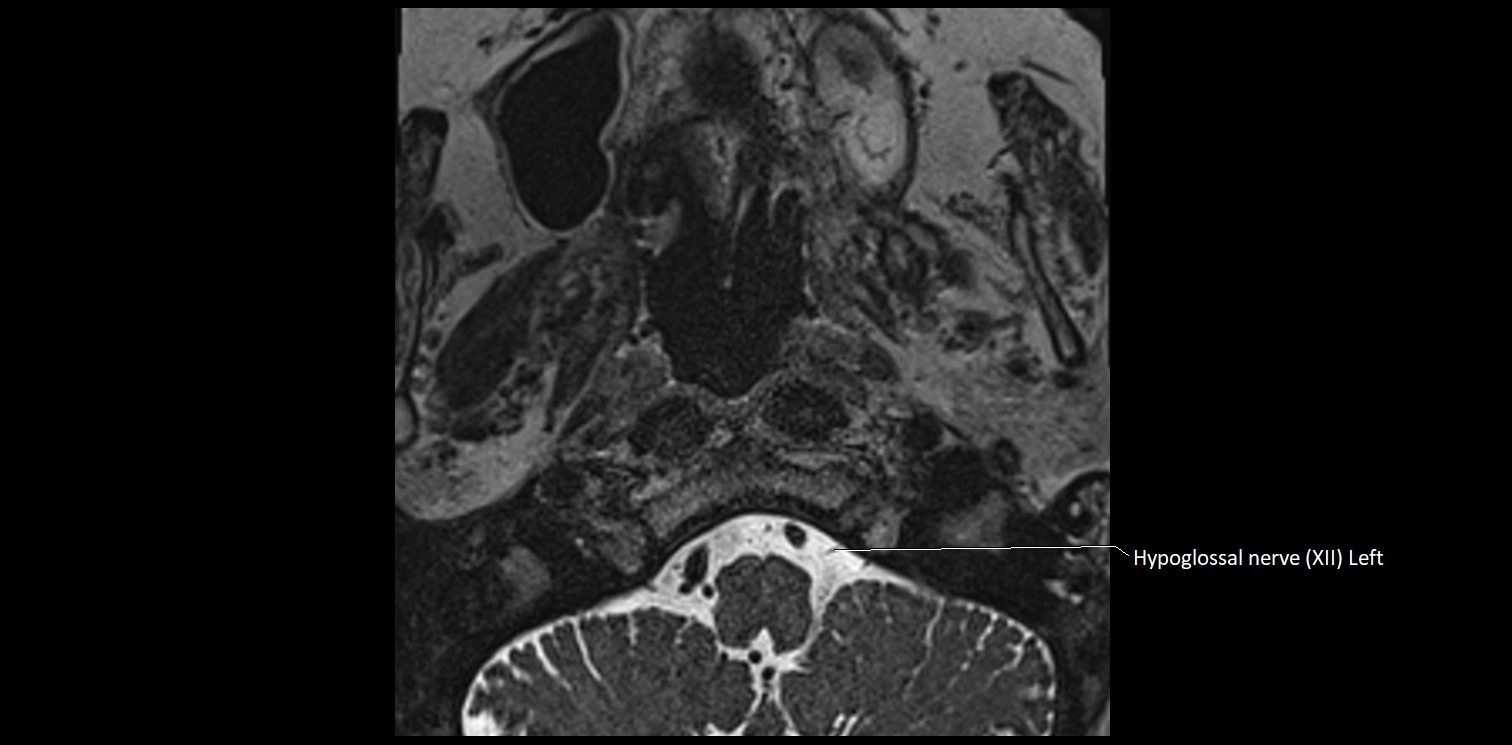

MRI Appearance

• The abducens nerve is a small, thin, linear structure

• Best visualized on high-resolution T2-weighted 3D MRI sequences (e.g., FIESTA or CISS)

• Seen as a hypointense (dark) line running from the brainstem at the pontomedullary junction, traversing the prepontine cistern, and entering Dorello’s canal under the petrosphenoidal ligament, then into the cavernous sinus, and finally the orbit

• May be challenging to visualize in standard MRI due to its small size

• Pathology may be inferred by absence, displacement, or enhancement of the nerve